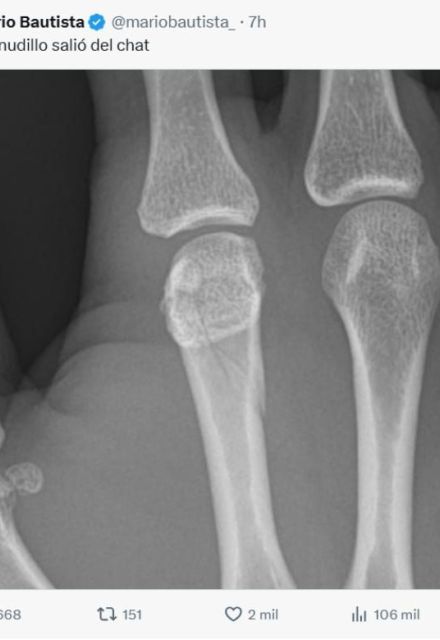

Después del evento, la conversación tomó otro rumbo cuando Mario Bautista compartió información sobre su estado físico. A través de su cuenta de X, el cantante publicó una imagen de una radiografía de su mano derecha acompañada del mensaje:

“Mi nudillo salió del chat”. Aunque la publicación fue eliminada horas más tarde, usuarios alcanzaron a analizarla.

En la imagen se apreciaba una posible fractura en el cuello del segundo metacarpiano, es decir, en el hueso que conecta el dedo índice con la muñeca. Este tipo de lesión se caracteriza por presentarse justo debajo de la cabeza del hueso y puede mostrar una ligera inclinación hacia la palma de la mano.

Especialistas suelen referirse a este tipo de daño como la “fractura del boxeador”, ya que ocurre cuando hay un impacto directo con el puño cerrado. Es una lesión común en disciplinas de contacto, lo que explicaría su aparición tras el combate.